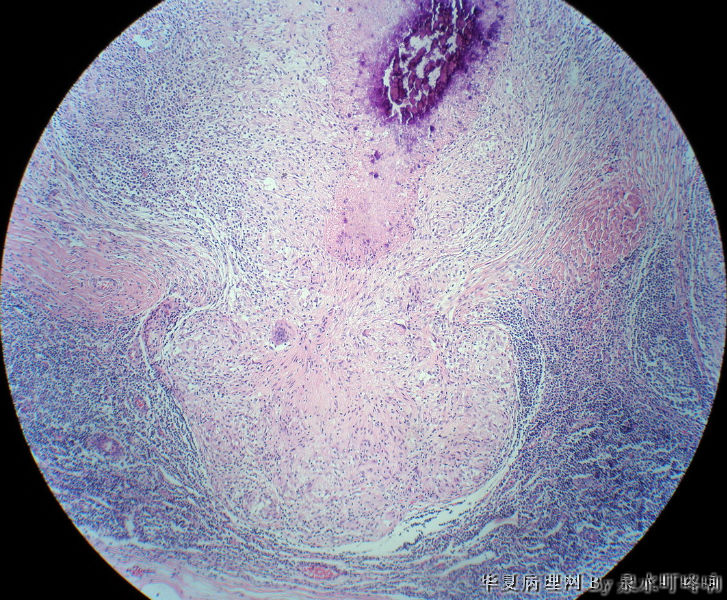

左腋窝肿物

• 左腋窝肿物图4

图4

女,3岁,主因左腋窝肿物半年,术中见为肿大淋巴结,淋巴结内有脓液及坏死组织。

大体:灰红色组织一块,大小约4.6×3.5×2厘米,切面可见两个囊性区域,内容乳白色浓稠液体。

肉芽肿性炎(建议做抗酸染色,除外结核)

是淋巴结吧,淋巴结肉芽肿性炎伴坏死,建议做抗酸染色。

肉芽肿性炎,考虑结核伴钙化。